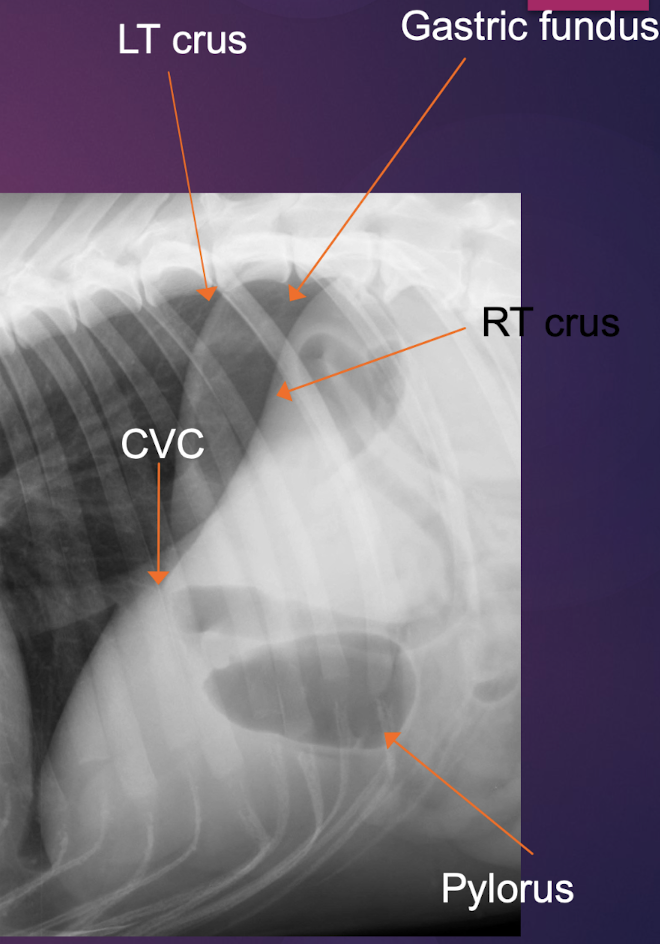

Q

Factors to point out Right lateral

A

-RT crus of diaphragm more cranial (caudal vena cava (CVC) enters RT crus)

-RT and LT crura are parallel to each other

-Gastric fundus caudal to LT crus

-Gastric fundus is gas filled (up side);pylorus is fluid filled (down side)

10

Right or left lateral?

Right